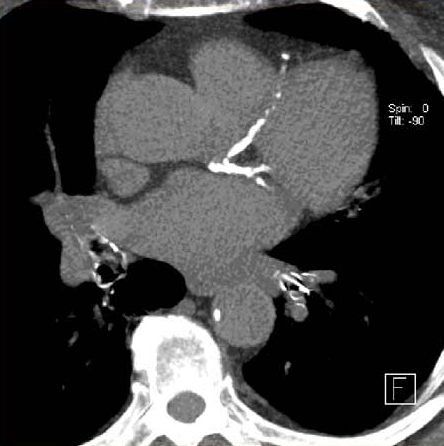

Evaluación con tomografía computada en pacientes con probabilidad intermedia de enfermedad coronaria derivados para angiografía

Sólo el 14% de los evaluados inicialmente con TC requirió angiografía coronaria invasiva; no hubo diferencias clínicas en el seguimiento a 3 años. BMJ, 24 de octubre de 2016